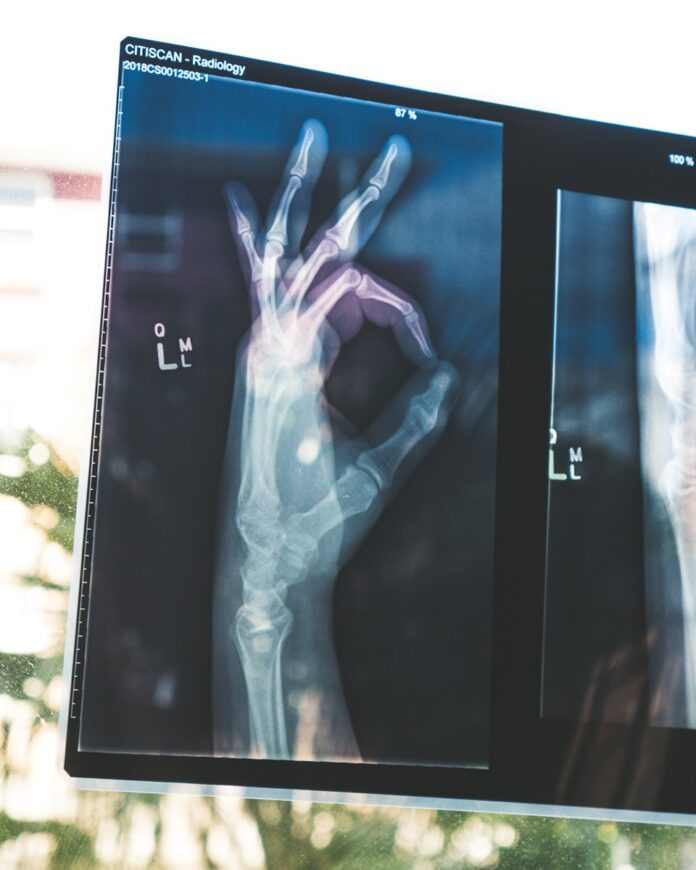

네 번째, 정기적인 골밀도 검사를 받는 것도 골다공증 예방에 도움이 됩니다. 특히 폐경 이후 여성이나 65세 이상 고령자는 1~2년에 한 번씩 검사해 뼈 건강 상태를 점검하는 것이 좋습니다.